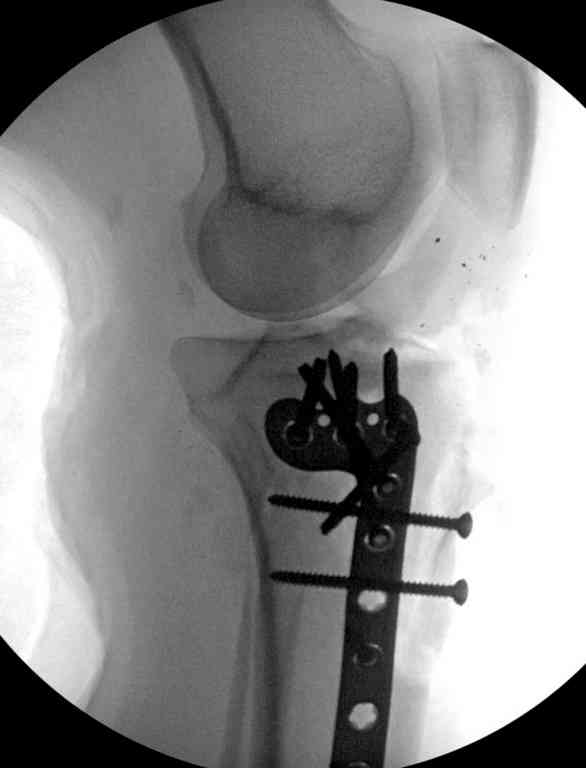

Здесь применение материала Plexur http://www.plexur.com для пластики при дефектах кости у больной с огнестрельной раной латерального тибиал плато с повреждением малоберцового нерва. Несмотря на интактный медиальный мышелок, для профилактики от вальгуса установлен АВФ и сделана ангиограмма.

После нескольких обработок и вакуумирования, поэтапно сделана фиксация тибиального бугра шурупами. И окончательную фиксацию закончили латеральной пластиной для тибиал плато и установкой пластического материала.